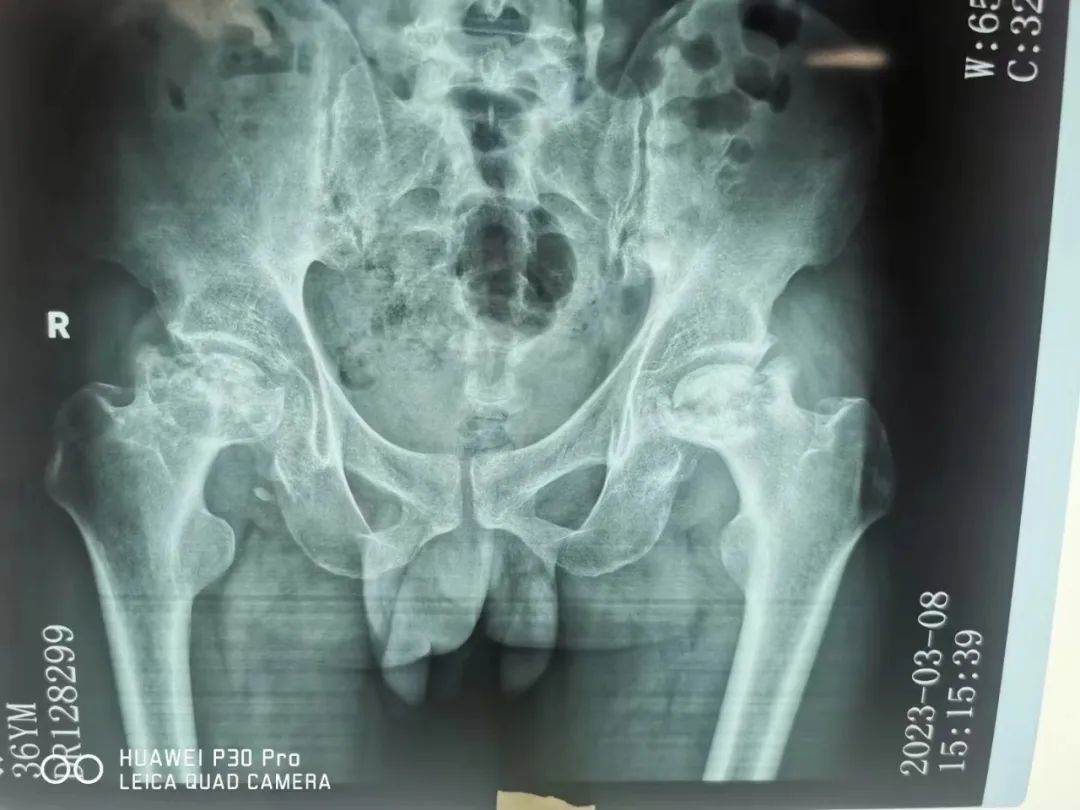

骨科团队对其进行了详细问诊及检查,影像资料显示张先生双侧股骨头坏死,右侧髋部坏死较严重,头部已全部塌陷,左侧股骨头坏死症状稍轻,但也出现了坏死情况,是不小的问题。如果病情继续恶化,下半生都要依靠轮椅了。

双侧股骨头坏死